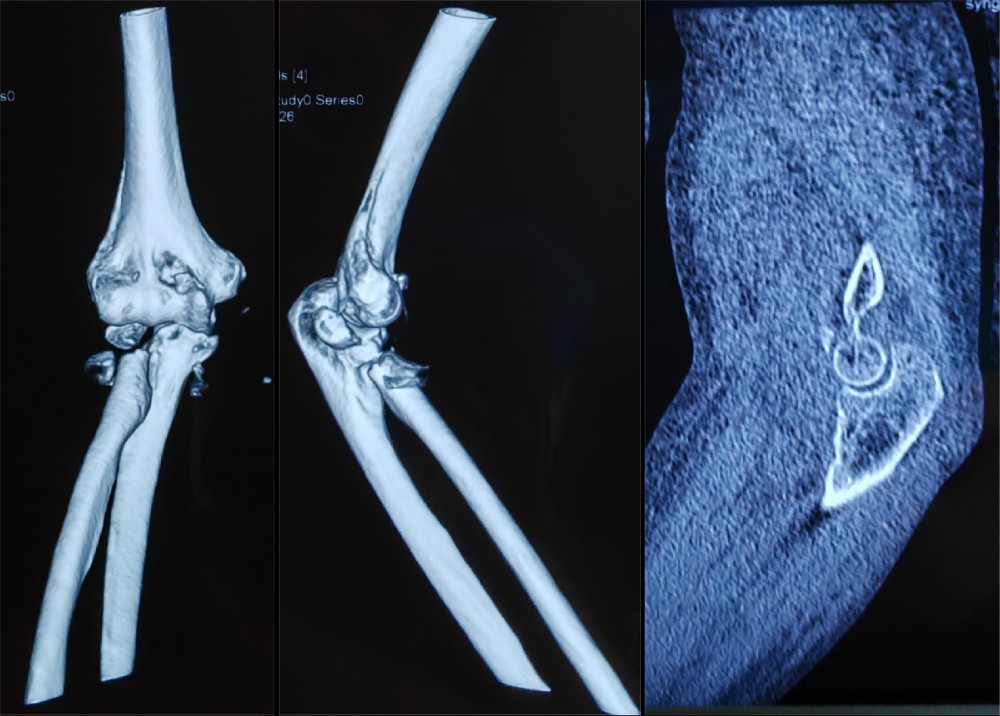

患者徐某,76岁,右肘部疼痛肿胀伴活动受限1天入院,患者于入院前1天,不慎被车从后侧撞伤,伤及右肘部,当时即感右肘部疼痛、畸形伴活动受限。受伤时患者否认头痛、头晕,胸闷、气短,恶心、呕吐等不适,被人救起后即赴某三甲医院就诊,行X光片检查显示:右肘关节脱位,右尺骨冠状突骨折,右桡骨头粉碎性骨折(肘关节恐怖三联征),给予手法复位肘关节脱位,患者为求进一步诊治赴91直播 门诊就诊,门诊以“1.右桡骨头粉碎性骨折2.右尺骨冠状突骨折”,收入91直播 创伤外科中心A区。

结合患者年龄及损伤类型,按照肘关节恐怖三联征的标准化治疗理念,副院长冯卫教授、创伤外科中心A区团队与李庭教授充分沟通、讨论后,由李庭教授及冯卫教授团队共同为患者施行标准化的治疗:“单一肘关节外侧切口,进行右冠状突骨折切开复位内固定术,右桡骨头粉碎性骨折桡骨头置换术,右肘关节外侧副韧带修复术,术中见右肘关节仍不稳定,随后给予右肘关节外固定架固定术”。标准化的治疗流程,使得这位高龄患者达到了与北京积水潭医院同质化的治疗。